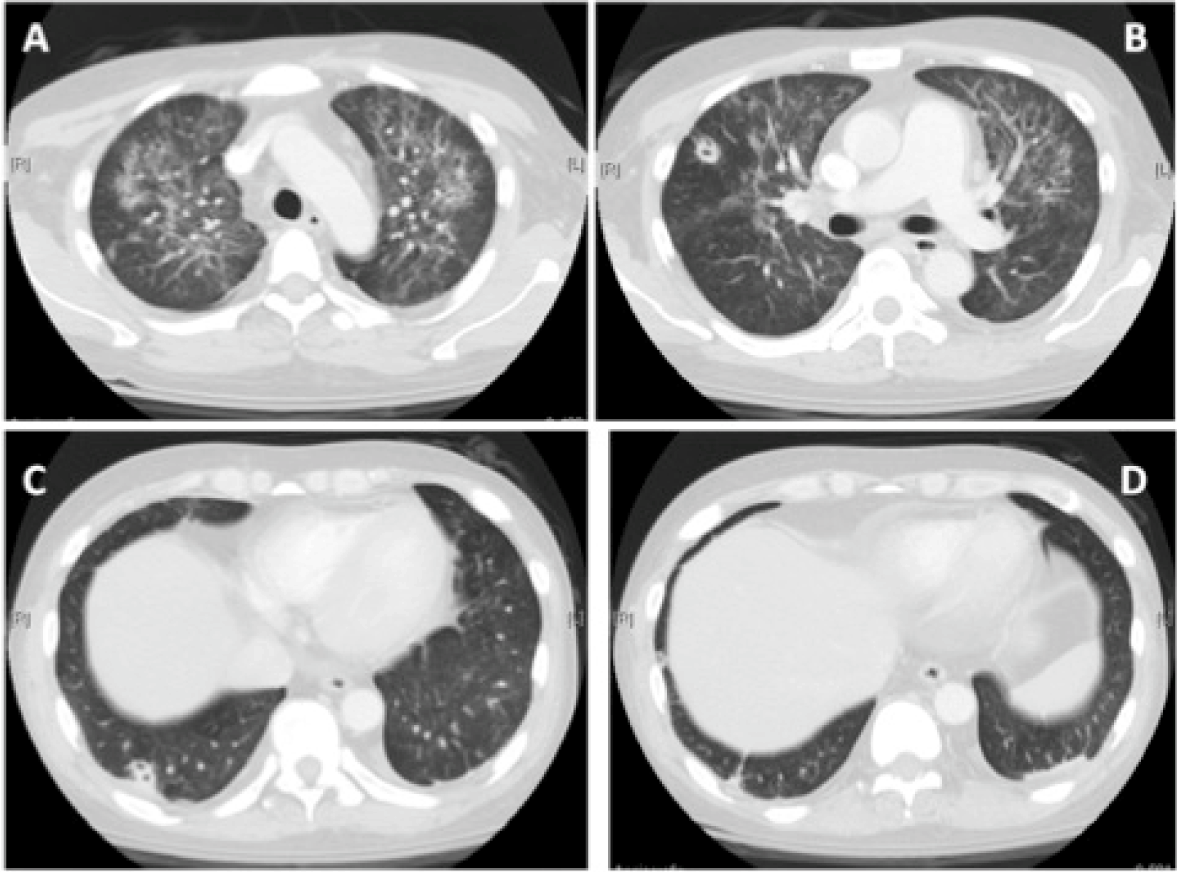

A 42-year-old male had medical history of immune thrombocytopenic purpura (ITP), chronic hepatitis C with liver cirrhosis, Child's-Pugh-Turcotte score A, and end stage renal disease requiring maintenance hemodialysis. The patient also suffered from multiple ecchymoses and tender plaques on all four limbs for one month. The lesions secreted bloody discharge (Figure 1A-D). Cellulitis was initially treated at our emergency department. The dermatologist suspected erythema induratum and suggested a skin biopsy. However, the procedure was postponed due to severe thrombocytopenia. Fever, chills, recent trauma, insect bites, pet contact, and travel history were all ruled-out. A high fever with chills started three days after treatment for cellulitis with empirical antibiotics (intravenous oxacillin: one gram every four hours). Ulcerative plaques with bloody discharge on all four limbs became gradually more severe. New ecchymotic nodules with pus occurred. The patient's vital signs were: blood pressure 166/108 mmHg, heart rate 106 beats per minute, respiratory rate 18 breaths per minute, temperature 39.3°C. The patient's blood workup revealed hemoglobin concentration of 7.7 g/dL, a leukocyte count of 13.3x103 cells/mm3 with an absolute neutrophil count of 87%, and a platelet count of 20x103 cells/mm3. C-reactive protein (CRP) was 69 mg/L. Chest radiography showed multiple nodules over the right upper lung and left upper lung, compared to previous radiographs (Figure 2). The patient did not have respiratory symptoms but was isolated because pulmonary tuberculosis could not be excluded. High resolution computed tomography scan showed a diffuse ground-glass picture over the central and upper lung, two cavitary lesions in the right middle lung (1.6 cm) and right lower lung (1.6 cm), and minimal pleural effusion (Figure 3A-D). The high fever and chills persisted after antibiotics were modified several times. A skin biopsy was performed, and pathology showed lobular panniculitis and a strong positive finding of acid-fast bacilli (Figure 4). A bone marrow biopsy also showed a strong positive finding of acid-fast bacilli but no granulomatous inflammation. Both biopsies had negative gram stains and periodic acid-schiff stain. Disseminated tuberculosis infection involving skin and bone marrow was suspected. Anti-tuberculosis (TB) medication, including rifampin 360 mg, isoniazid 240 mg, and pyrazinamide 150 mg per day, was started. The high spiking fever persisted and new plaques with discharge continued to occur. After a four-day course of anti-TB medication, hyperbilirubinemia (total bilirubin: 2.5 mg/dL and direct bilirubin: 1.64 mg/dL) and hyperuricemia occurred. The anti-TB medication protocol was modified as follows: rifampin 600 mg, INH 300 mg and EMB 800 mg per day. Anti-TB treatment was stopped due to progressive jaundice. After 8 days of observation, hepatic function improved, and rifampin 450 mg, INH 200 mg per day and EMB 800 mg per two days was started. It was frustrating that the intermittent fever persisted and the skin lesions healed poorly after anti-TB treatment continued for two months. Unfortunately, the dose could not be increased due to hepatic function. A culture of bone marrow and sputum showed the presence of Mycobacterium haemophilum approximately 82 and 98 days later. Therefore, the final diagnosis was disseminated Mycobacterium haemophilum, which involved the skin, bone marrow, joints and lung. The antibiotics were changed to rifabutin 300 mg per day and clarithromycin 500 mg every twelve hours. After that, the fever subsided and treatment was continued for one year. The patient received regular outpatient department follow-up every three months and no pus or ulceration was noted. | ||||||